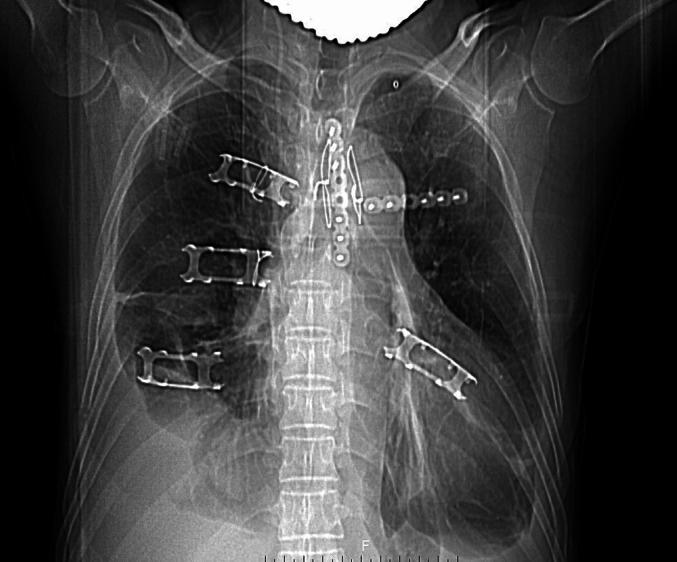

A 53-year-old male patient with sternal manubrium avulsion fracture and costal cartilage fractures caused by a bull goring injury was treated with a multi-material combined fixation strategy (wire cerclage reduction + titanium plate and screw fixation + memory alloy embracing device). The wire threading technique and flexible costal cartilage fixation technique were optimized during the surgery.

The surgery successfully achieved stable fixation of the sternum and costal cartilage, with postoperative CT showing good alignment and disappearance of paradoxical breathing. The patient did not undergo any loosening of the internal fixation, recovering smoothly.

The combined application of wire cerclage, plate fixation, and memory alloy internal fixation can effectively treat sternal manubrium avulsion fractures combined with flail chest.

方法

结果

结论